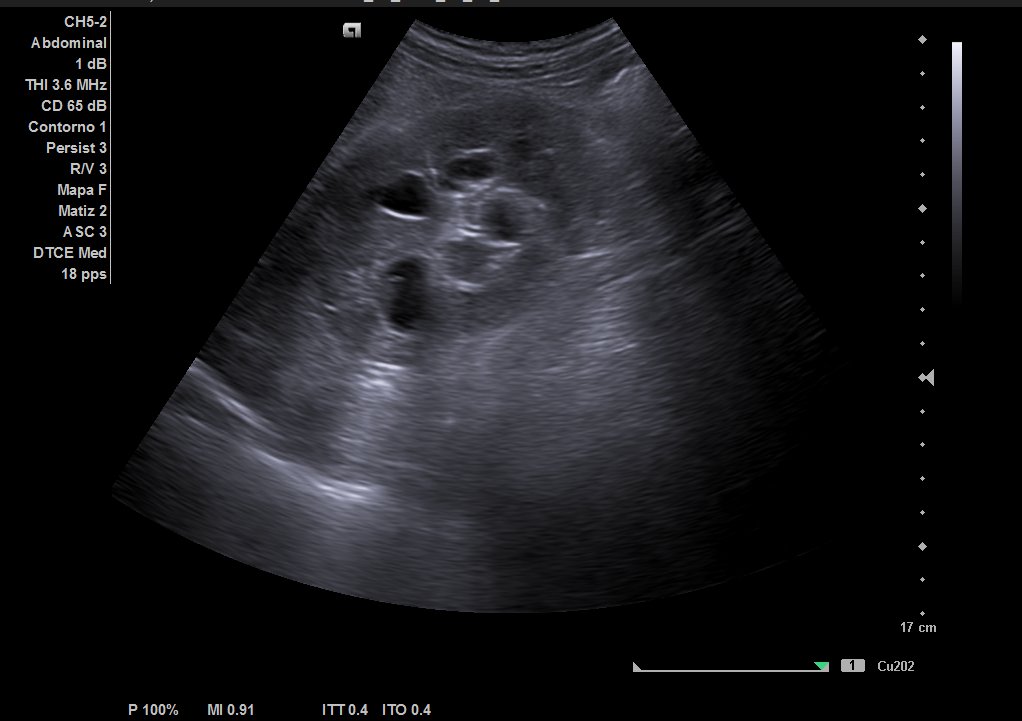

Ecografía urinaria: vejiga bien replecionada, observándose masa en trígono de 20 x 12 mm. Riñón derecho con dilatación pielocalicial moderada, sin hidronefrosis. Riñón izquierdo sin alteraciones reseñables.

Ecografía reglada: ureterohidronefrosis grado III secundaria a lesión en uréter medio-distal. Vejiga parcialmente replecionada con material ecogénico en suelo vesical con aparente doppler color e interior. Posible coágulo vs lesión subyacente.